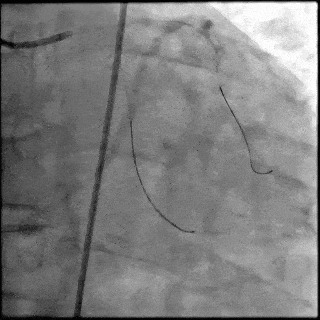

【DSA图3.回旋支导丝顺利通过病变】

5月28日8:00,葛均波院士团队在中山医院16号楼16楼中伟厅成功连线喀什二院导管室,沪喀远程手术正式开始。8:35,新疆喀什二院导管室内股动脉入路通路建立后,行左右冠脉造影示左前降支中段存在85%的严重狭窄,狭窄位于血管分叉路口且紧邻心肌桥;且左回旋支中段近乎闭塞,血管细窄且迂曲,病变弥漫。8:59,葛院士于上海操控血管介入机器人主端PANVIS COF,将指引导管送至左冠脉开口,并操控主支导丝和分支血管保护导丝通过狭窄病变,后送至前降支和对角支血管远端以建立轨道,同时利用介入机器人的微速调整功能避开心肌桥,以亚毫米级精准定位释放1枚支架。在成功处理患者左前降支病变后,葛院士通过搓捻机械操纵杆,远程精细调整导丝“进攻”方向,顺利通过左回旋支次全闭塞病变。因血管相对细小且病变弥漫,葛院士决定采用单纯球囊扩张术处理,即刻造影提示几乎无残余狭窄,避免了额外的支架植入。10:10,撤出所有导丝及导管,手术顺利结束。